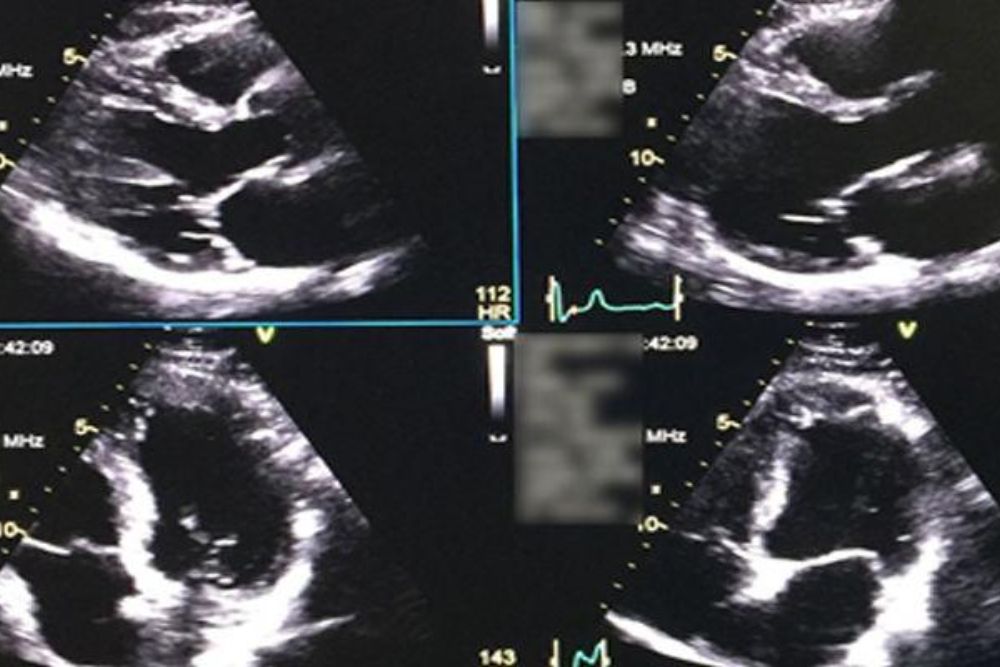

2-D-Echo

A 2-D Echo is an ultrasound test that provides real-time images of the heart, helping diagnose structural abnormalities, valve issues, and overall heart function.